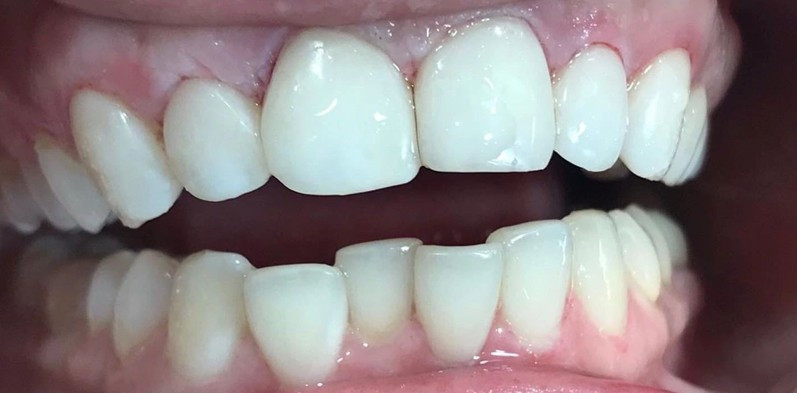

Профгигиена

Жемчужная чистка зубов

Доктор: Евченко Надежда Владимировна